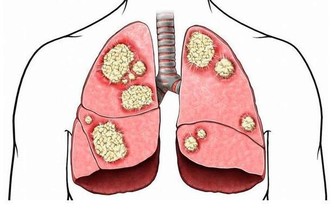

患有鼻炎、鼻竇炎、扁桃體炎等上呼吸道疾病,則會散發出一股腥臭味。

有胃潰瘍、胃炎、胃食管反流等毛病,胃裡消化發酵的氣體排到了口腔裡,則表現為酸臭味。

糖尿病患者,由於沒有足夠胰島素分解醣類,會開始分解脂肪來提供能量,分解物之一的酮體濃度增加,就會產生一股爛蘋果味。